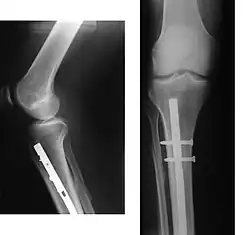

При наличии показаний к операции методом выбора может быть эндопротезирование суставов. В настоящее время разработаны и успешно применяются эндопротезы тазобедренного и коленного суставов. При остеопорозе эндопротезирование осуществляется конструкциями с цементным креплением. Дальнейшее консервативное лечение коленного сустава способствует снижению сроков реабилитации оперированных больных и повышению эффективности лечения.